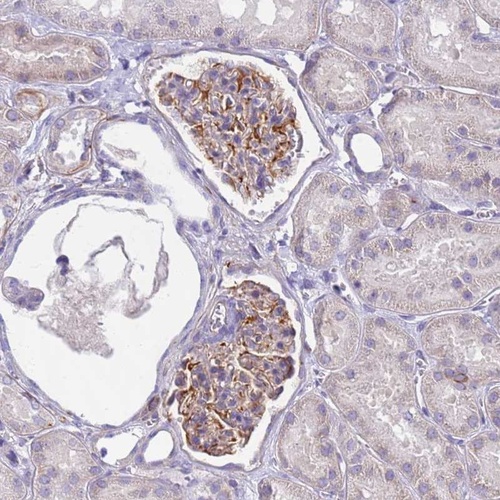

Immunohistochemical staining of human kidney shows distinct cytoplasmic positivity in glomerular cells.